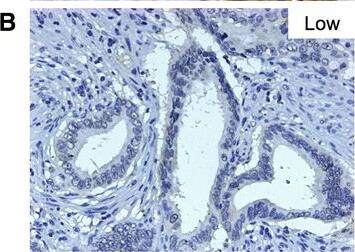

Nectin-4 antibody in Human Placenta by Immunohistochemistry (IHC-P).

Nectin-4 in Human Placenta.

Nectin-4 was detected in immersion fixed paraffin-embedded sections of human placenta using 10 µg/mL Goat Anti-Human Nectin-4 Antigen Affinity-purified Polyclonal Antibody (Catalog # AF2659) overnight at 4 °C. Before incubation with the primary antibody tissue was subjected to heat-induced epitope retrieval using Antigen Retrieval Reagent-Basic (CTS013). Tissue was stained with the Anti-Goat HRP-DAB Cell & Tissue Staining Kit (brown; CTS008) and counterstained with hematoxylin (blue). View our protocol for Chromogenic IHC Staining of Paraffin-embedded Tissue Sections.